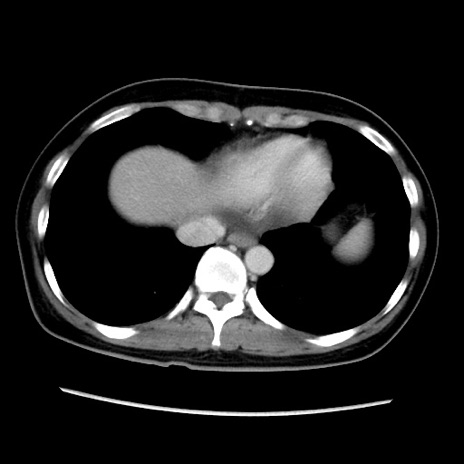

症例39(横断像)

【症例】40歳代女性

【主訴】上下腹部痛

【現病歴】2日目から下腹部痛あり。夜間は痛みで眠れなかった。昨日より上腹部痛と下痢が出現。臥位で痛みは軽快したため、休んでいた。本日になって臥位でも立位でも痛みが強くなってきたため救急要請。

【既往歴】子宮内膜症

【身体所見】部:平坦・軟、左上下腹部に圧痛あり、反跳痛あり。

【データ】WBC 21800、CRP 26.78